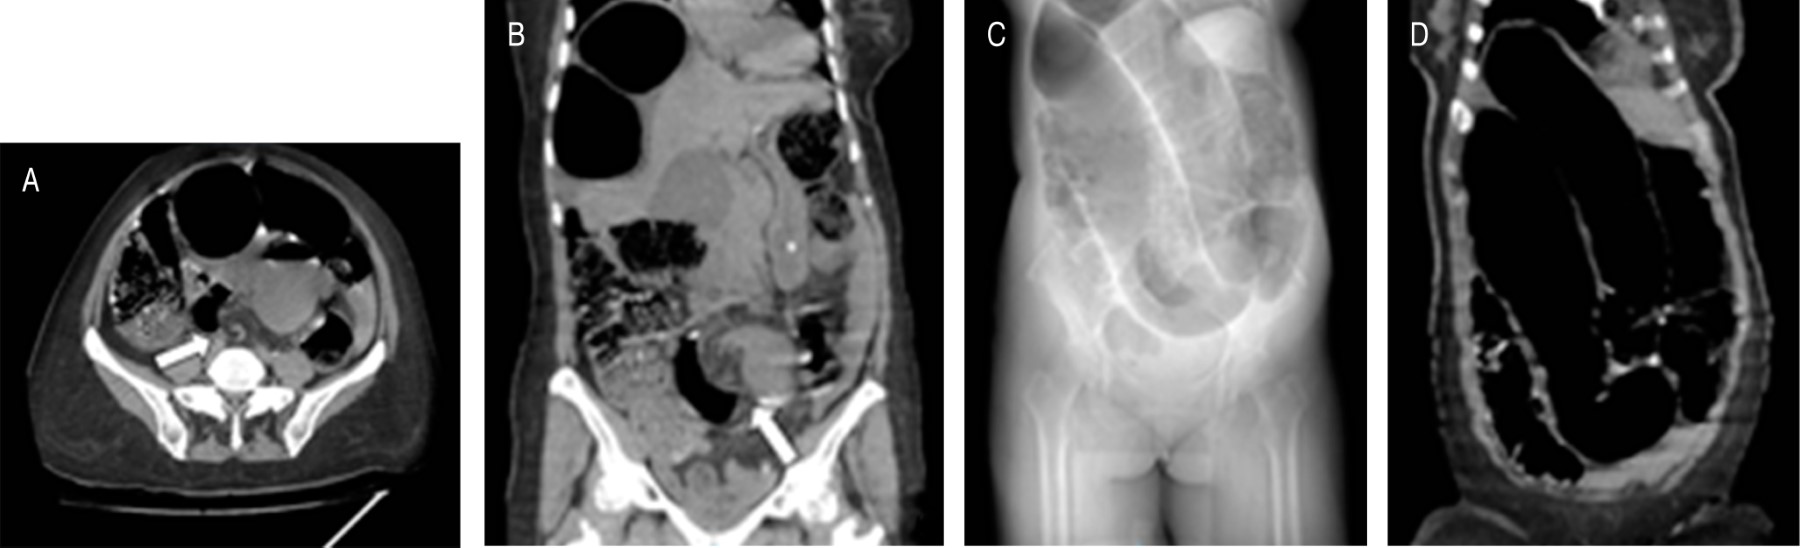

En la radiografía simple, la clave diagnóstica para el vólvulo sigmoideo es el colon dilatado sin haustras, con forma de "U" invertida y localizado en la línea media con dirección hacia los cuadrantes superiores. El signo del "grano de café" se produce debido a la imagen central creada por el contacto de las paredes mediales del asa volvulada y las paredes laterales que dan lugar a los bordes del grano (Figura 1).3 Sin embargo, sólo el 60% de los pacientes se logra diagnosticar mediante radiografía abdominal. La presencia de neumatosis lineal sugiere perforación inminente por necrosis intestinal; la presencia de aire libre sugiere perforación intestinal.11

El estudio de elección es la tomografía computarizada debido a su sensibilidad de 100% y especificidad > 90%, debido a que permite crear reconstrucciones multiplanares que facilitan el diagnóstico definitivo.1 Los hallazgos son superiores a los de la radiografía simple; los signos específicos tanto de la tomografía como de la radiografía para vólvulos sigmoideo y colónico se muestran en la Tabla 2.3,11 No obstante, hasta 25% de los pacientes no presentaron estos signos característicos (Figura 1).